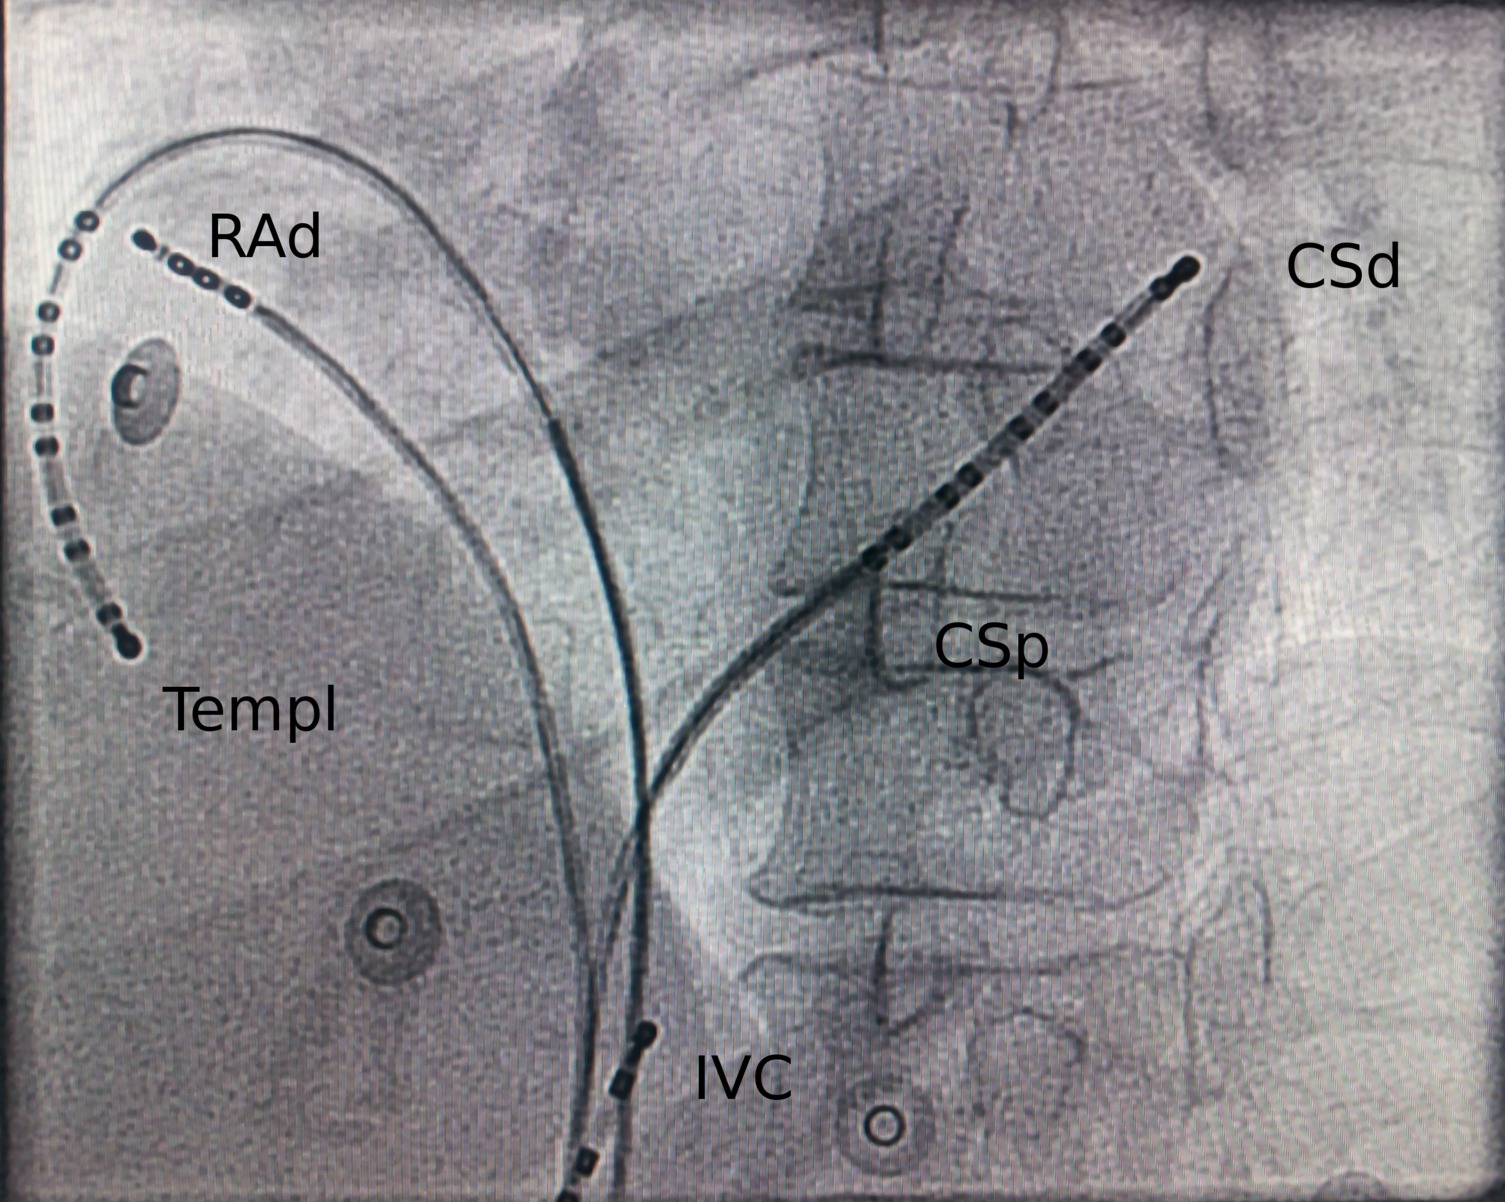

Widely spaced bipolar EGM

Fig1.jpg

Selvaraj RJ et al. Pace mapping in the atrium using bipolar electrograms from widely spaced electrodes. Journal of Arrhythmia 2015; 31: 274-278

fig4.jpg